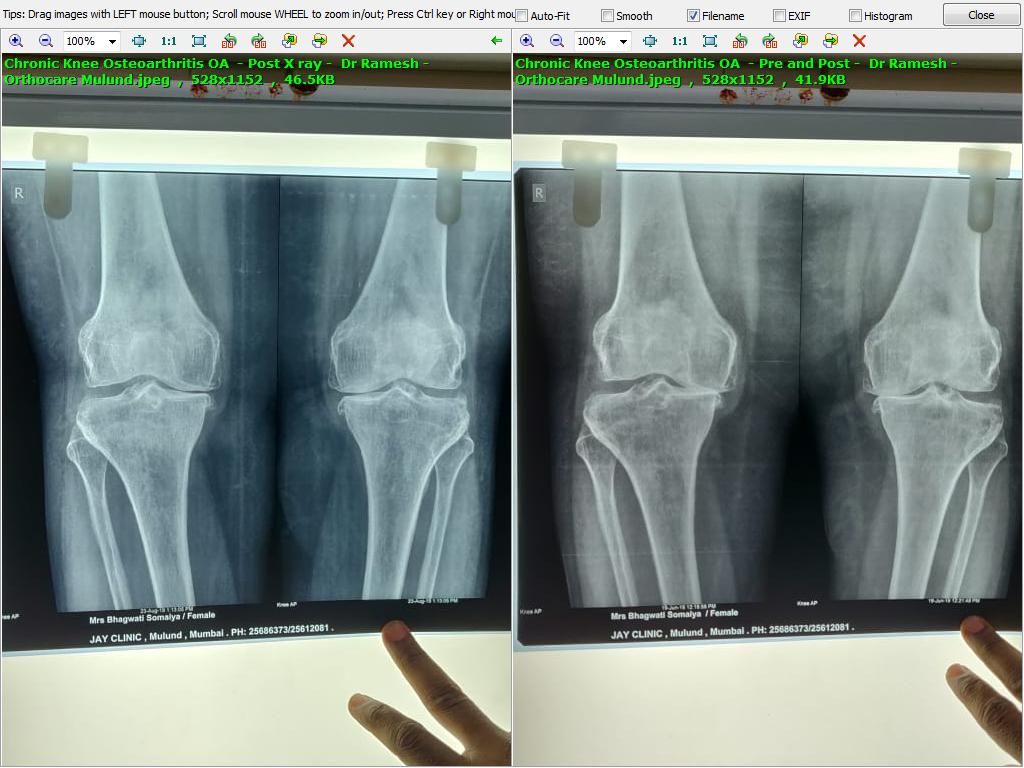

Osteoarthritis OA TKR - Total Knee Replacement averted Dr Ayaz Mumbai